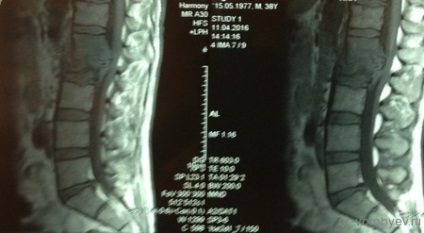

Pacientul sa plâns de dureri la nivelul coloanei vertebrale cervicale care radiază brațele. El a fost tratat într-un spital neurologic, în cazul în care RMN-ul a aratat inflamatie a vertebrelor.

Doar după terapia cu antibiotice masive, pacientul a suferit o intervenție chirurgicală: corporectomy C6, C7. Cage Corporodesis alunecare (corp vertebral protetice) ADD + Ulrich, Germania și înlocuitor de os de corali. Pe CT de control în picioare implanturi decompresie corectă, adecvată.